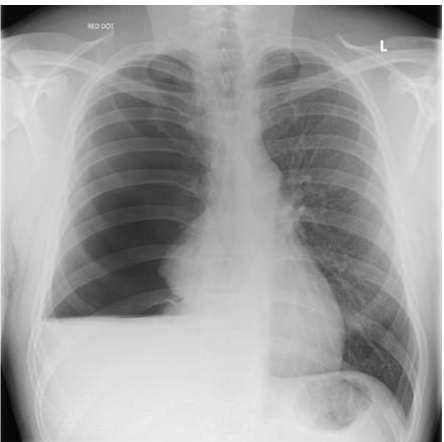

whats the dx

left: normal

right: atelectasis

atelactasis has

_______ opacity

costophrenic angles _____

________ of ribs

potential mediastinal shift to ____ side

atelactasis:

homogenous opacity

costrophrenic angles blunted

crowding of ribs

potential mediastinal shift to SAME side

the mediastinum shifts to the (same/opposite) side in atelectasis. why?

same; when the lung collapses, it acts as a vacuum and sucks everything to the same side